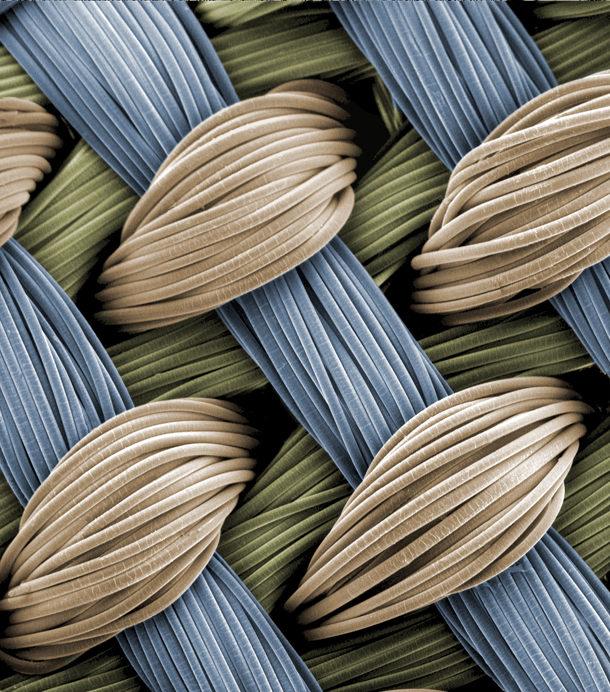

Tiny interwoven fibers make up the three-dimensional fabric scaffold into which a strong, pliable hydrogel is integrated and injected with stem cells, forming a framework for growing cartilage. This image appears on the cover of the Dec. 17, 2013, issue of Advanced Functional Materials. (Credit: Frank Moutos, Farshid Guilak)

In 2007 Guilak and his team developed a three-dimensional fabric scaffold into which stem cells could be injected and successfully “grown” into articular cartilage tissue. Constructed of minuscule woven fibers, each of the scaffold’s seven layers is about as thick as a human hair. The finished product is about 1 millimeter thick.